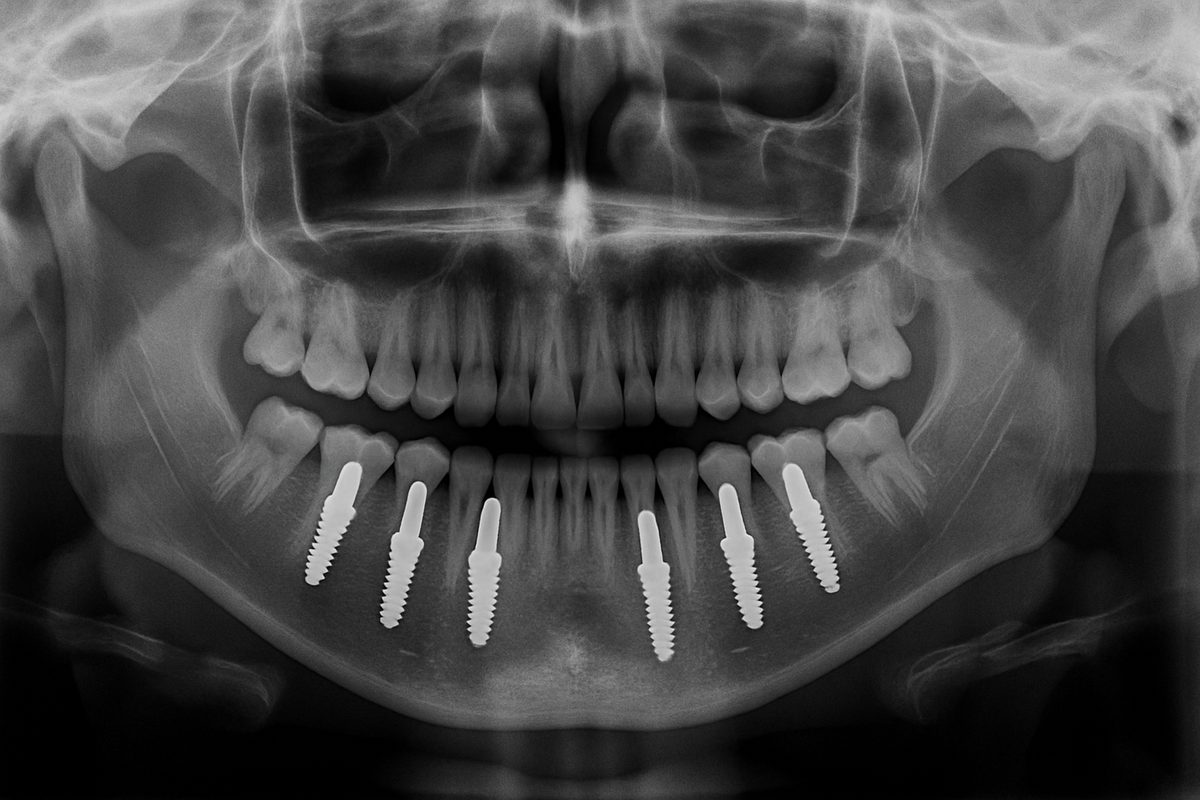

Dental implants are titanium posts placed into the jaw to act like tooth roots, topped with a tooth crown or dental bridge. Dental implants restore chewing power, feel and look like natural teeth, and help preserve jawbone. With good care, dental implants often last 15–30+ years. Maintenance includes regular brushing, flossing, and dental checkups.

Single dental implants replace one tooth; multiple dental implants support bridges; All-on-4 or All-on-X replace full arches. Mini dental implants are smaller posts for limited support or narrow spaces. Immediate placement means a dental implant is placed right after extraction; delayed placement waits for healing or grafting. Choice depends on bone volume, health, and how many teeth are missing.